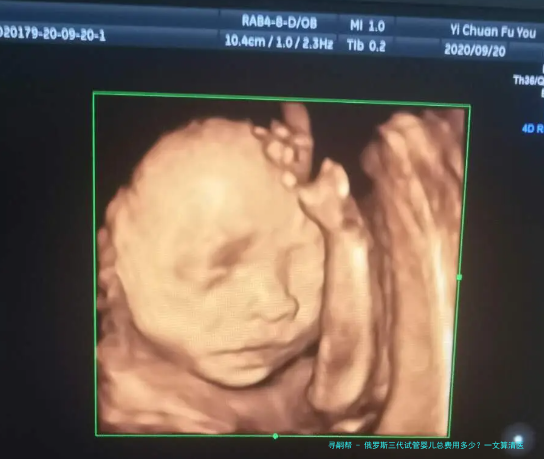

俄罗斯三代试管婴儿总费用多少?一文算清医疗和生活全账单

跟着人类辅助生殖技术的不断发展,越来越多的家庭选择通过试管婴儿技术来实现生育愿望。俄罗斯以其先进的医疗科技和相对偏低的费用,吸引了许多国内患者前往就诊。如此,俄罗斯三代试管婴儿的总花销究竟是多少呢?本文将为您详细梳理俄罗斯三代试管婴儿的医疗费用和赡养费用,让您对整个流程的花费胸有定见。

俄罗斯三代试管婴儿的总费用受到多种因素的影响,包括病人的身体状况、选择的医院和医生、促排卵方案以及需不需要进行PGS/PGD基因筛查等。通常来讲,1个周期的俄罗斯三代试管婴儿总花销大致在15万到30万人民币之间。这个费用涵盖了医疗费用用和在俄罗斯期间的生活费用,但具体金额还需要按照个人情况进行整合。

俄罗斯三代试管婴儿的总费用大致在15万到30万人民币之间,其中看病费用用约占8万-20万人民币,生活费用约占7万-10万人民币。具体费用会受到医院选择、促排方案、PGS/PGD筛查等因素的影响。在进行俄罗斯三代试管婴儿前,建议充分了解各个环节的费用,并做好充分的资金准备,选择正规机构,确保整个过程顺利进行。